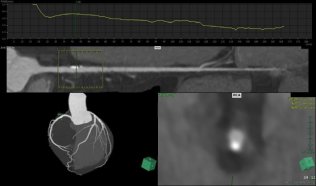

- シャントPTA

| 血管透析には1分間に約 200ml という量の血液量が必要となります。 この血液量を得るために動脈と静脈をつなぎ合わせシャントを作成します。このシャントが狭窄すると血管透析をすることができなくなります。 血管造影にて血管狭窄の有無を診断し、狭窄が見られた場合はバルーン(風船)で拡張し、治療します。 |

||

|

|

| 治療前 | バルーン拡張 | 治療後 |